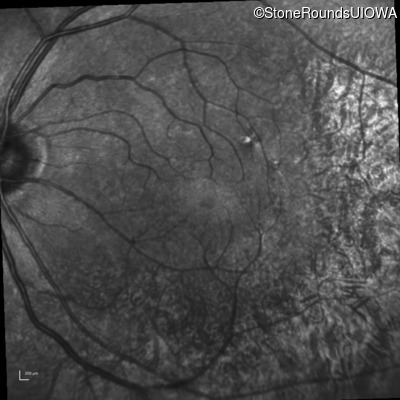

Infrared Fundus Photograph - Right - 20/20

Exemplar